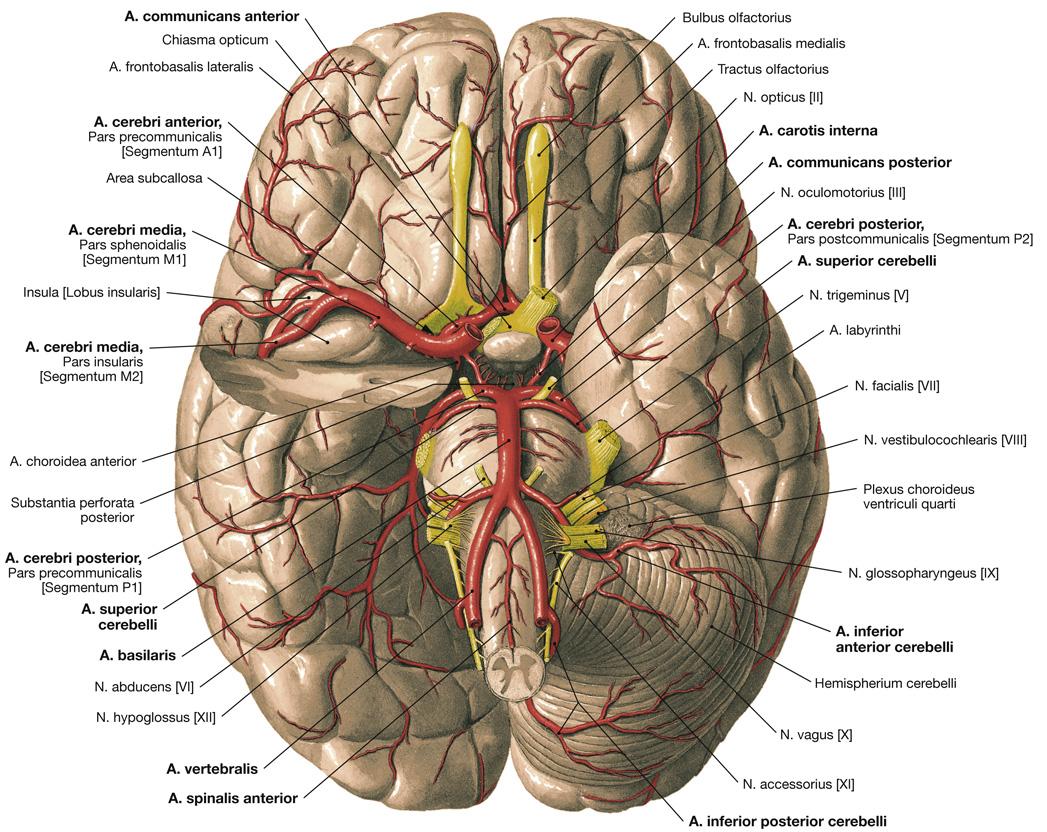

Fig 3.11: a. carotis interna

-

schedelbasis

-

a carotis communis

-

cirkel van Willis

details: zie neuro a vertebralis > a basilaris > a cerebri posterior a carotis interna > a cerebri media a carotis interna > a cerebri anterior a carotis interna > a communicans posterior a communicans anterior